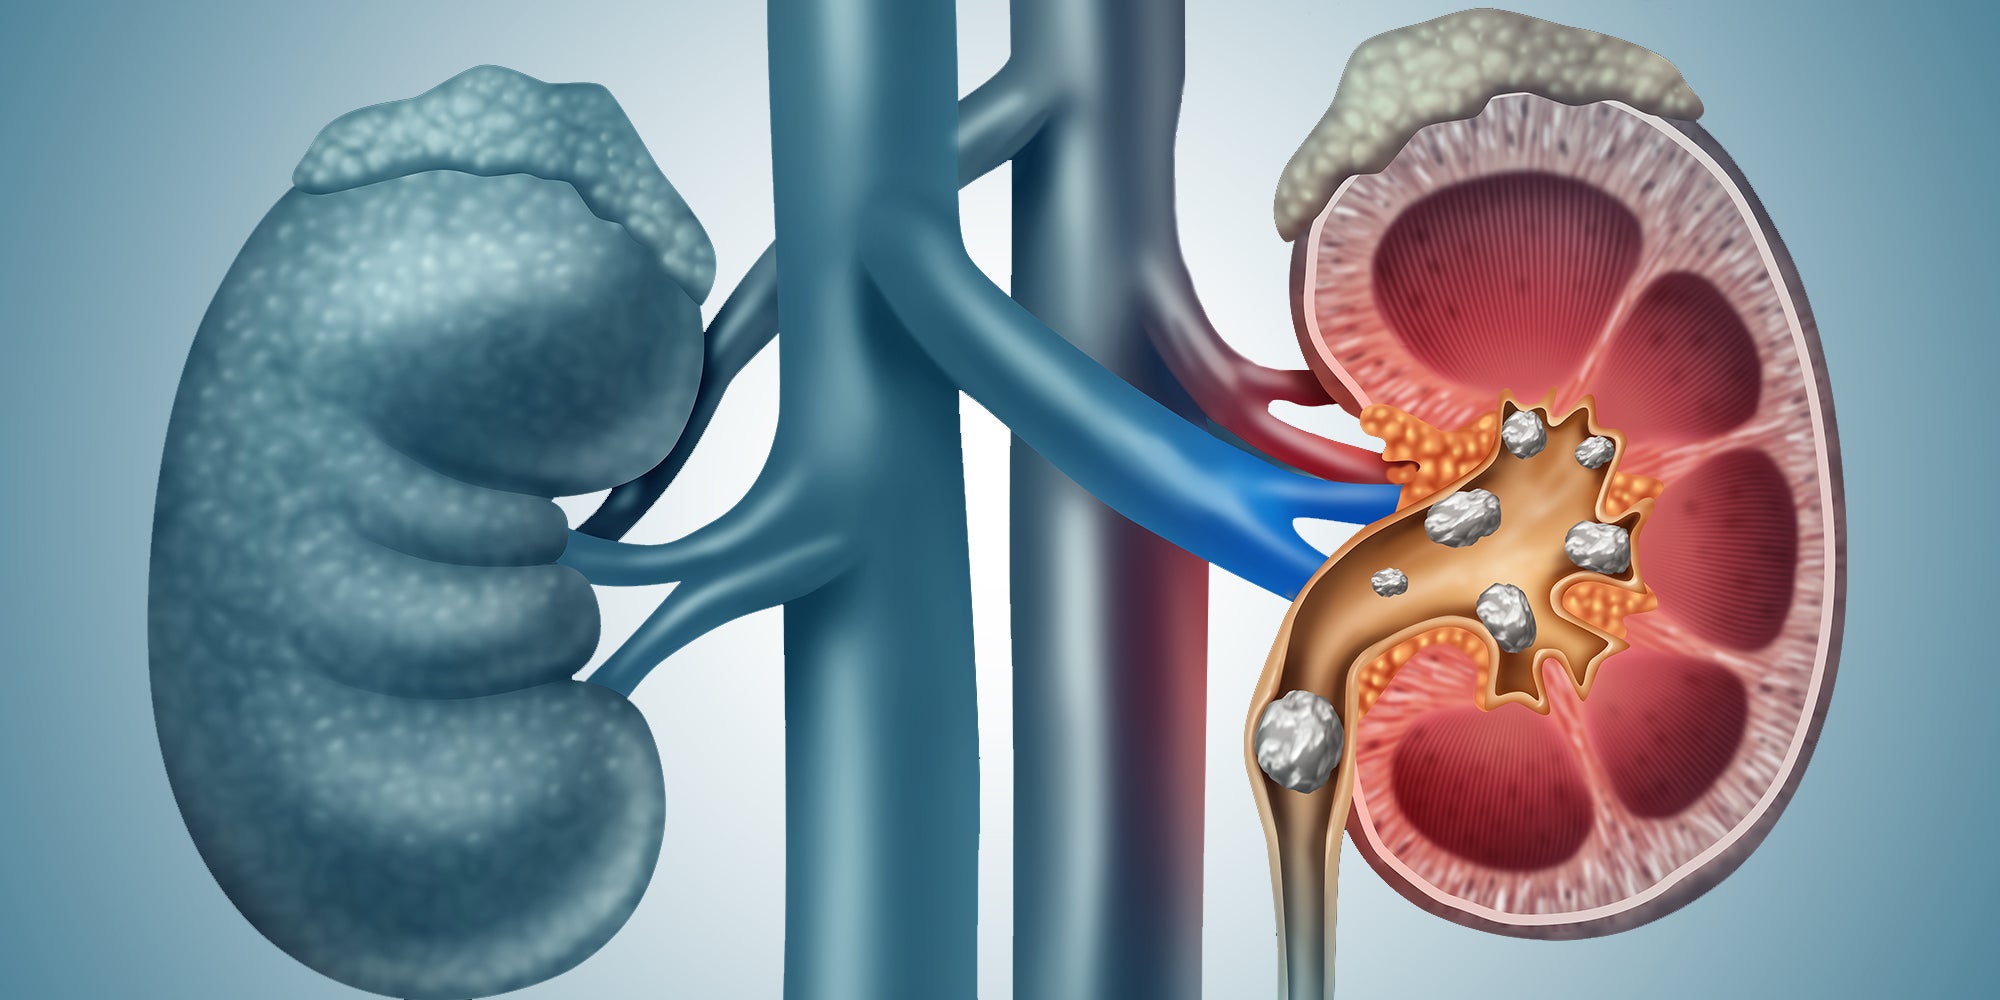

How to know if you have kidney stones discount, Symptoms of Kidney Stones discount

Signs You May Have Kidney Stones Blog Loyola Medicine- how to know if you have kidney stones